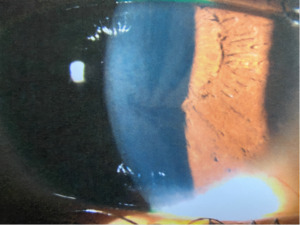

Follow-up Visit #2

At the 2-week follow-up appointment, the patient reported that the spot was gone and denied any other ocular or visual complaints. Vision and slit lamp findings were stable in both eyes. Undilated fundus evaluation was remarkable for mild vessel tortuosity in both eyes and complete resolution of the vitreous hemorrhage in the right eye (Figure 3).

Blood plasma testing confirmed a below-normal level of α-galactosidase A consistent with heterozygous Fabry disease. Upon receiving the confirmatory laboratory results, the patient was educated about the disease and treatment options, including enzyme replacement therapy. She was medically discharged from the Navy, referred to her primary care physician, and advised to return annually for eye examinations or sooner if any changes in vision were noted.